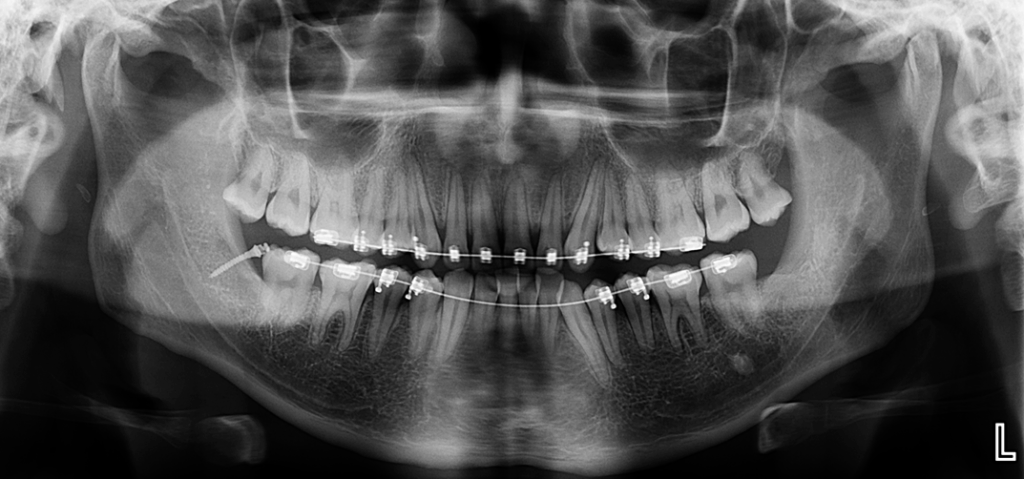

En la radiografía panorámica (Figura 1), se aprecia imagen radiopaca proyectada sobre línea media.

A la evaluación de la tomografía volumétrica (CBCT) en los cortes axiales (Figura 2) y transaxiales (Figura 3), se aprecia pieza supernumeraria en posición invertida localizada en zona anterior del maxilar superior, así mismo se observa disminución de la densidad a nivel coronario y reabsorción radicular externa a nivel del tercio cervical (ameloclasia).

CORTES TRANSAXIALES

caso 328 idm cortes tangenciales